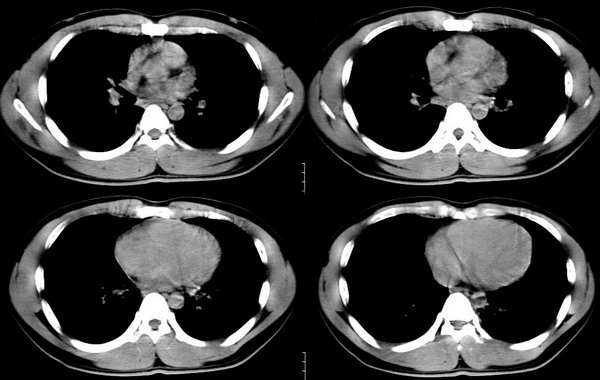

以下是引用ssl1_1在2006-3-2 22:37:00的发言:[br]肺泡蛋白沉积症(外围型)

以下是引用huangaiying1在2006-3-3 16:03:00的发言:[br]双肺弥漫分布的磨玻璃影及小结节影,以双上肺为著,纵隔内未见明显增大的淋巴结影,结合病史,考虑过敏性肺炎

以下是引用guandong在2006-3-4 20:57:00的发言:[br]两肺弥漫分布磨玻璃影,以中外带为主,可见于过敏性肺炎、肺泡蛋白沉着症、农民肺等,但不支持结核。